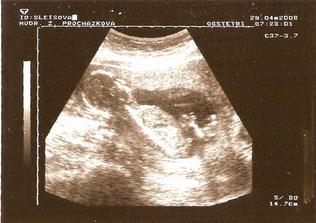

29.4.2008 - na utz se byl podívat i manžel, mimísek měří kolem 10 cm a kope! Je už nádherný.